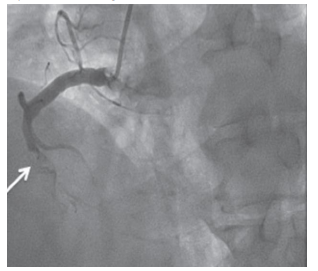

Assumindo que o achado na coronariografia (incidência oblíqua anterior esquerda) aconteceu agudamente, sua ocorrência é compatível com a emergência cardiovascular

Enunciado 3940738-1